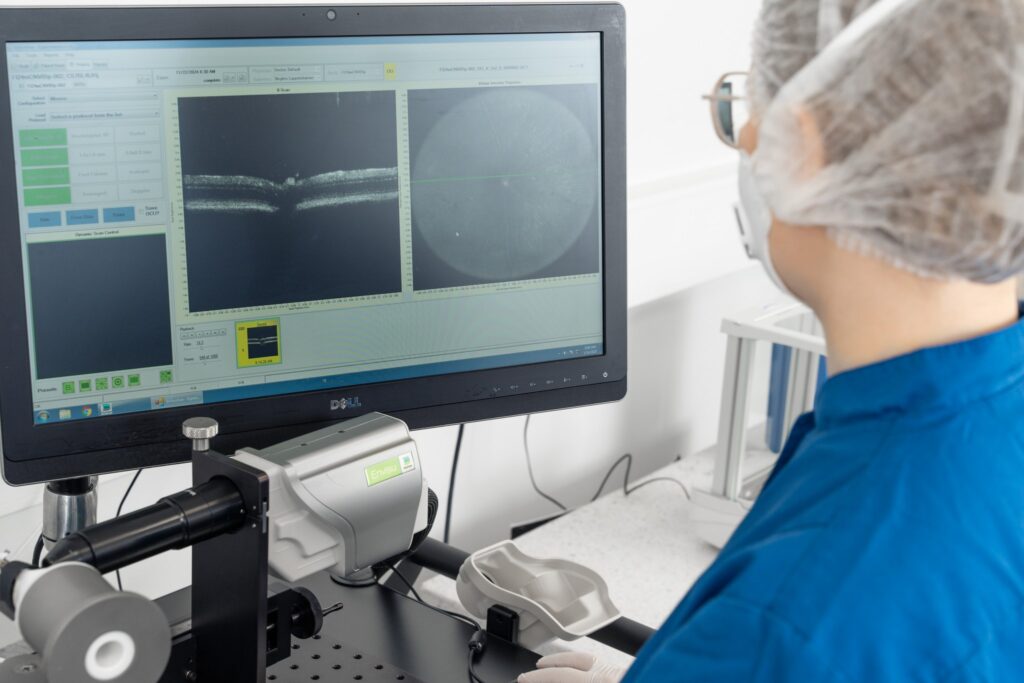

At Experimentica, we have implemented and validated both mouse and rat OIR models with a clinically relevant reference compound making them ideal for screening anti-angiogenic drug candidates. Our capabilities include morphological analysis of retinal vasculature from flat mounts, combined with in vivo imaging, such as fluorescein angiography (FA) and flash electroretinography (ERG).

In vivo imaging (FA, rat model)

Non-invasive in vivo imaging techniques and high-quality tissue samples to detect efficacy

Experimentica offers extensive in vivo imaging capabilities for high-resolution ocular assessments across species.